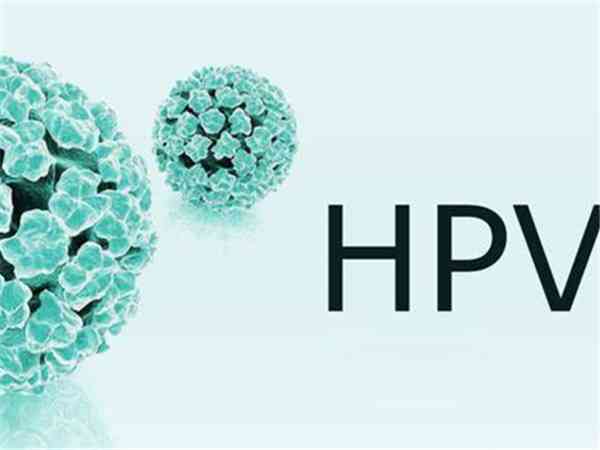

hpv感染十五年了一直没检查要注意,会不会癌变这篇说清

hpv感染是需要引起重视的,大多数是没有临床症状的,但是如果HPV持续感染,尤其是HPV16型HPV18型感染,引起宫颈癌的几率相对要大一些。hpv感染十五年了不一定发生癌变,此病毒分为高危型和低危型,低危型HPV病毒的感染,通常不会导致癌变,高危型HPV病毒的持续感染十五年了一直没检查可能发生癌变。